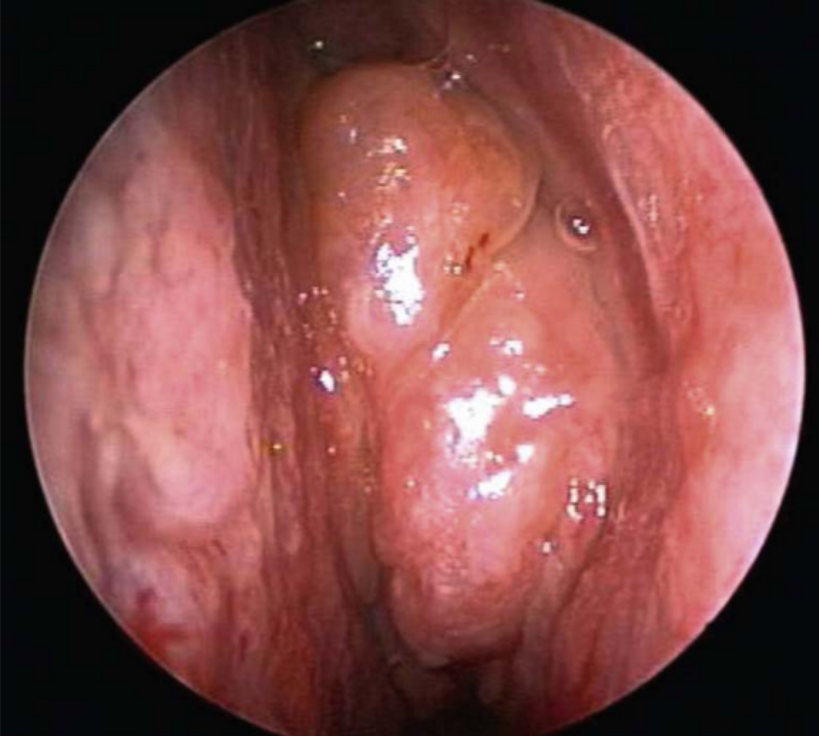

Endoscopic signs include nasal polyps , mucopurulent discharge (primarily from the middle meatus), and mucosal edema (also primarily in the middle meatus). CT findings include mucosal thickening of the paranasal sinuses and osteomeatal complex and fluid or debris in the paranasal sinuses (opacification).

These patients tend to have significant burden of polyps and over a prolonged period of time the thick, eosinophilic mucin can act as a benign soft tissue denisty in the paranasal sinuses with possible expansion into nearby structures, including the orbit and cranium. Treatment is with a combination of medical and surgical therapy, similar to other cases of chronic sinusitis. Neither systemic or topical antifungal therapy has been shown to improve treatment outcomes in this population.

Aspirin exacerbated respiratory disease (AERD) is a subset of CRS characterized by nasal polyps, aspirin sensitivity, asthma, and eosinophilic CRS. Previously known as Samter’s triad, AERD is now the more accepted term for this important condition. This triad, or more accurately tetrad, is present in approximately 10% to 25% of patients with CRSwNP and 25% to 40% of patients with CRSwNP and asthma. These patients are thought to have a dysfunction in the arachidonic acid metabolism pathway, with a resultant increase in the proinflammatory leukotrienes and a decrease in the anti-inflammatory prostaglandins both in serum and respiratory mucosa. Bronchospasm, mucosal edema, and an influx of eosinophils results when exposed to aspirin or nonsteroidal anti-inflammatory medications. These patients also tend to have more severe polyposis than others with CRSwNP. In addition to standard treatment for CRSwNP, aspirin desensitization is often a therapeutic option.